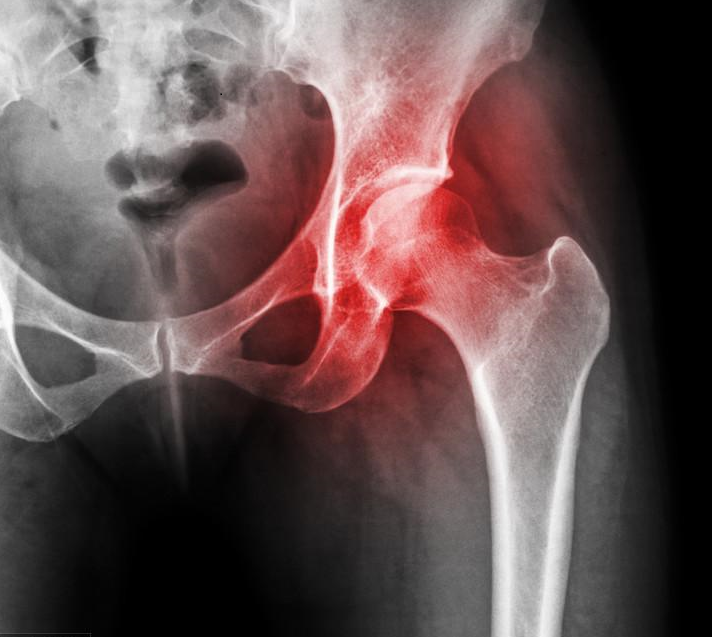

3.股骨頭壞死:太多朋友問股骨頭壞死能不能吃了。遺憾的告訴大家,作用及效果不大,尤其是X光片已經(jīng)發(fā)現(xiàn)囊性變的患者。股骨頭壞死有很多的分型,比如創(chuàng)傷型(就是骨折后形成的),這種源于骨折引起血運(yùn)不佳,從而壞死。所以營養(yǎng)軟骨是沒用的,而是需要盡早改善血運(yùn)和代謝。

股骨頭壞死